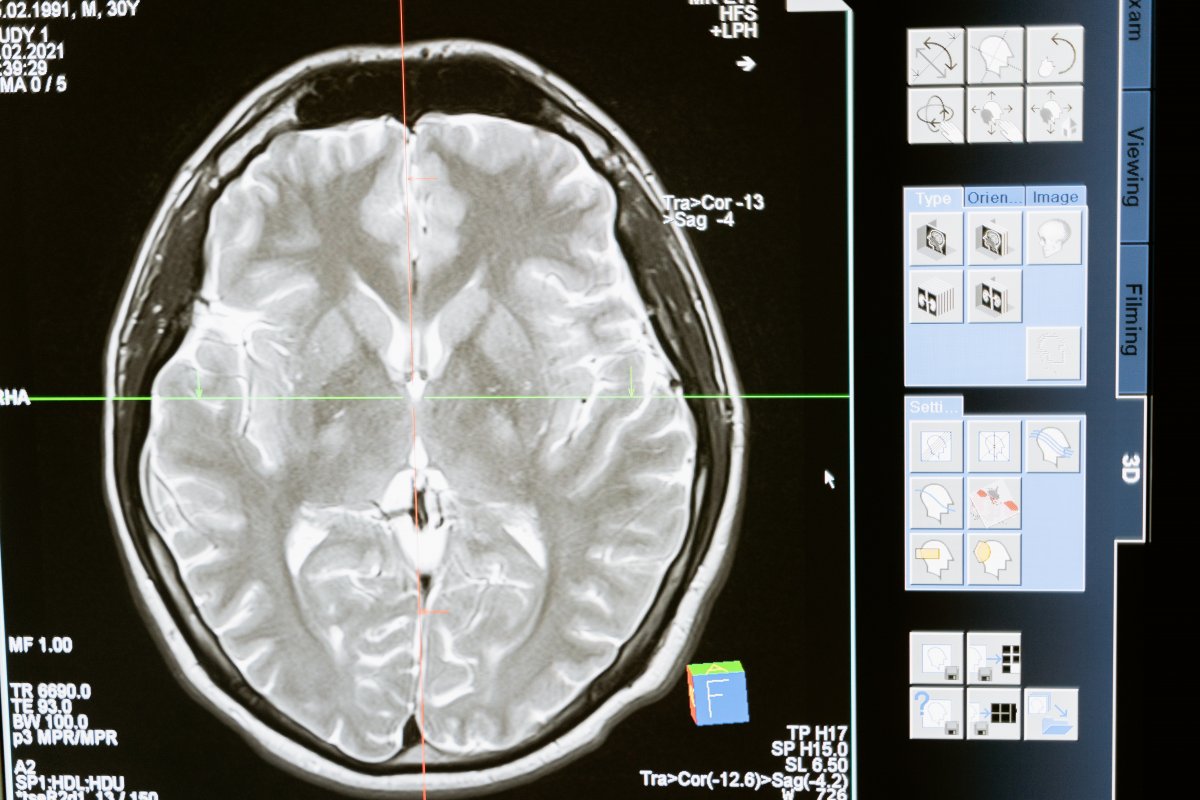

Foto: Pexels